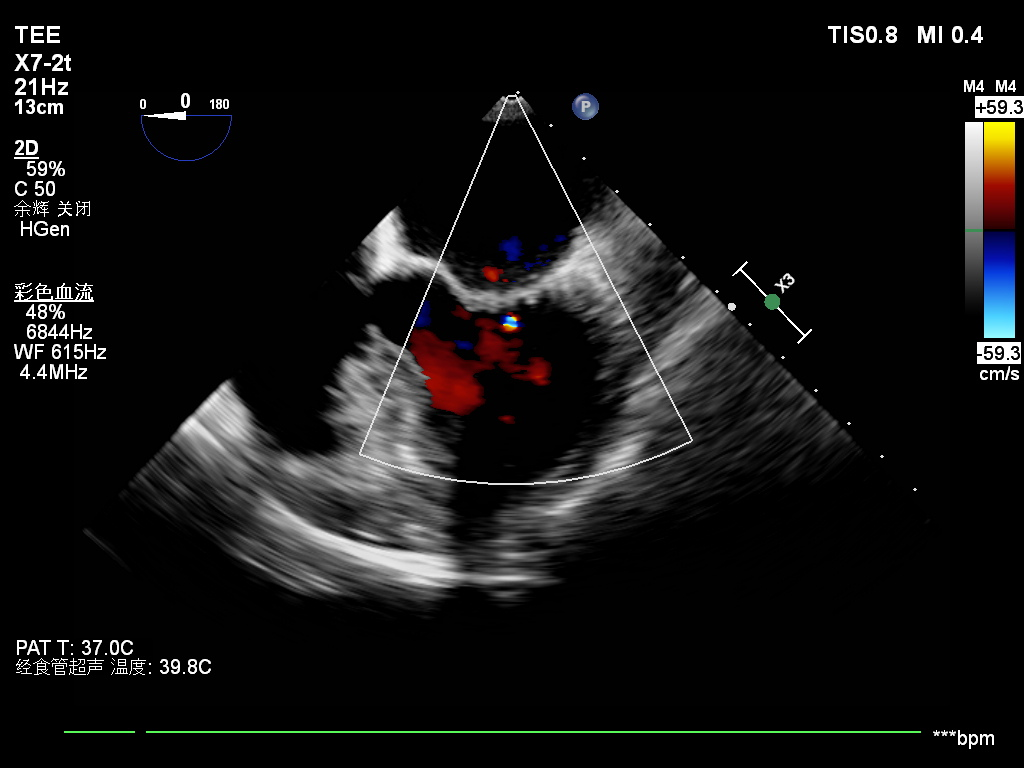

张海波教授接诊王女士后,对其心脏瓣膜情况进行了详细评估,认为修复可能性很大。手术由张海波教授亲自主刀,在体外循环下,精细清除瓣叶钙化组织,将增厚瓣叶逐层削薄,小心切开瓣交界粘连,同时将二尖瓣后叶予以补片加宽,置入成形环,整个过程如行云流水,一气呵成。试水见瓣膜关闭良好,术中同时为患者施行了房颤外科消融手术。术后心脏恢复良好,食道超声提示:二尖瓣成形效果理想,仅见微量反流,心律也恢复为正常窦性。

一台成功的成形术离不开外科医生、麻醉师、体外循环师、超声医师的紧密配合,术中需借助经食管超声实时监测修复效果,确认瓣膜反流是否消除、开闭是否正常,有时甚至需在心脏复跳后再次评估,若效果不佳还要再次停跳调整,这对整个团队的默契度与协同能力提出了极高要求。